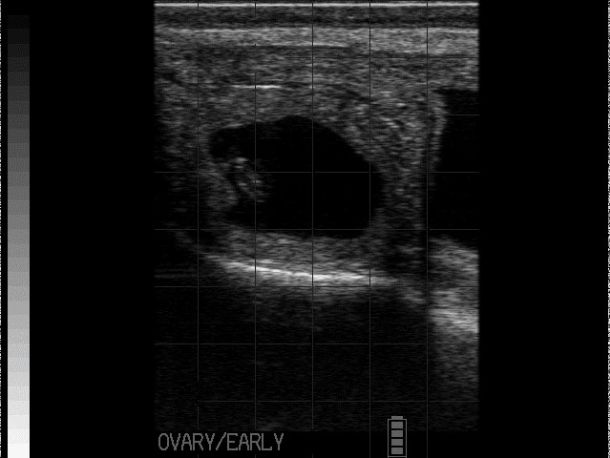

Follicular cysts are typically large, thin-walled (<2-3mm), round, black structures that are often single but can be multiple (see Photo 1)2,4. Traditionally, follicular cysts were defined by being greater than 25mm in diameter and persisting for longer than 10 days but recent work would indicate that follicular cysts can be present and only measure 16-17mm in diameter2. Cows with follicular cysts will have low peripheral progesterone concentrations and typically present anoestrous but can be nymphomaniacal if the cyst is actively secreting oestradiol4. However, that stated, follicular cysts are still dynamic structures which can luteinise (forming a luteal cyst), or become inactive and regress. In situations where they have begun to regress, the cystic structures can be noted in cows who have started to cycle again (i.e., some of these cows will have CLs) or even those cows who have become pregnant.

Luteal cysts are typically grey, thick-walled (>3mm walls), large fluid-filled structures (≥ 25mm) that are often single2. As noted, luteal cysts result from luteinisation of follicular cysts that fail to ovulate. Cows with luteal cysts will have high peripheral progesterone concentrations and typically present as anoestrous4.